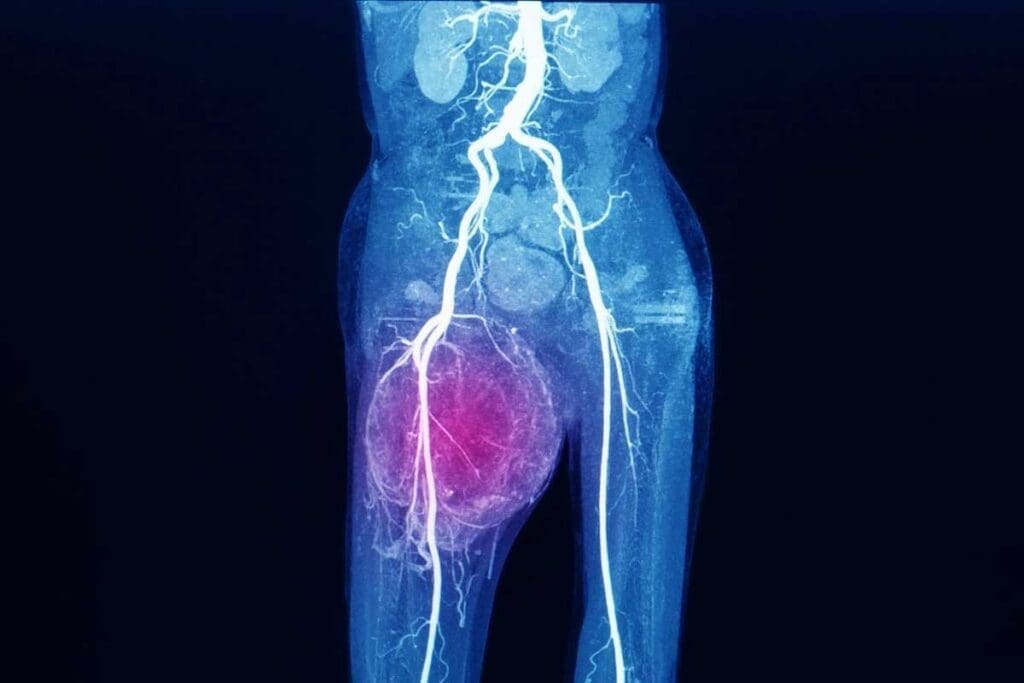

Imaging Techniques and Their Findings

Imaging is key in diagnosing Ewing sarcoma. X-rays, MRI, and CT scans help see the tumor and how big it is. These tools help doctors:

- Determine the tumor’s size and location

- Check if the tumor is touching nearby tissues or bones

- Look for any cancer spread to other parts of the body

Experts say, “Imaging is vital for staging Ewing sarcoma and planning treatment.” It not only helps in diagnosing but also in tracking how well the treatment is working.